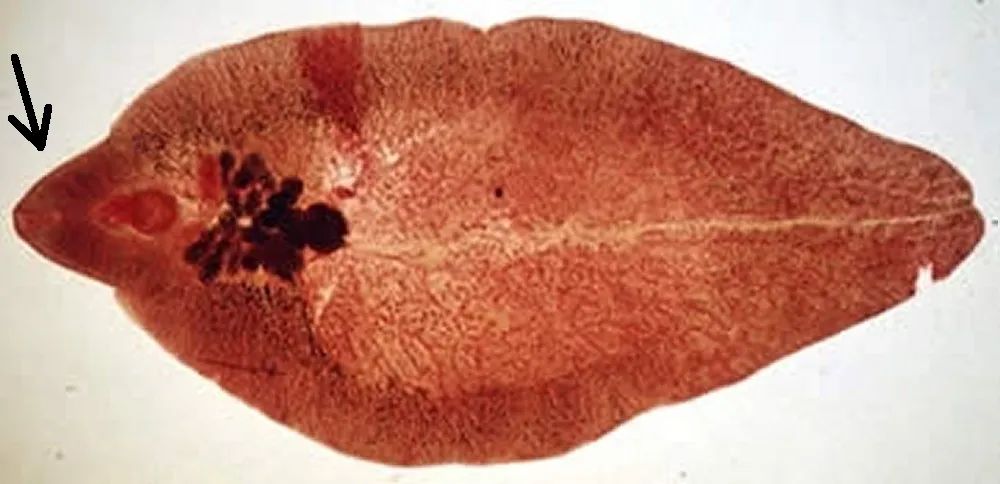

肝片状吸虫呈叶片状,前部有圆圈状纹理,看起来酷似多宝鱼,知道肝片状吸虫最大有多大吗?普通成虫可以长到3厘米长和2厘米宽,但是最大的成虫可以长到7.5厘米,有手指头那么长,俸女士身体内取出的肝片状吸虫明显就比较大个。

肝片状吸虫前部顶端长有一个小而有力的吸盘,看起来像鱼嘴一样,吸嘴就长在吸盘内,吸嘴从肝脏中吸食血液、胆汁和组织碎片,后端有多个排泄孔,用于排泄废物,肝片状吸虫还属于雌雄同体动物,可以实现有性繁殖或无性繁殖。